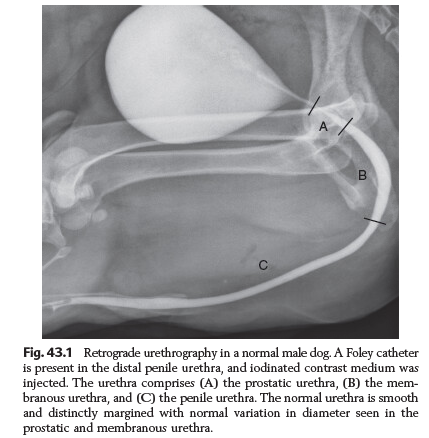

Three parts of the urethra?

Prostatic

Membranous

Penile

Retrograde urethragram is done with what type of contrast?

Iodinated, water soluble